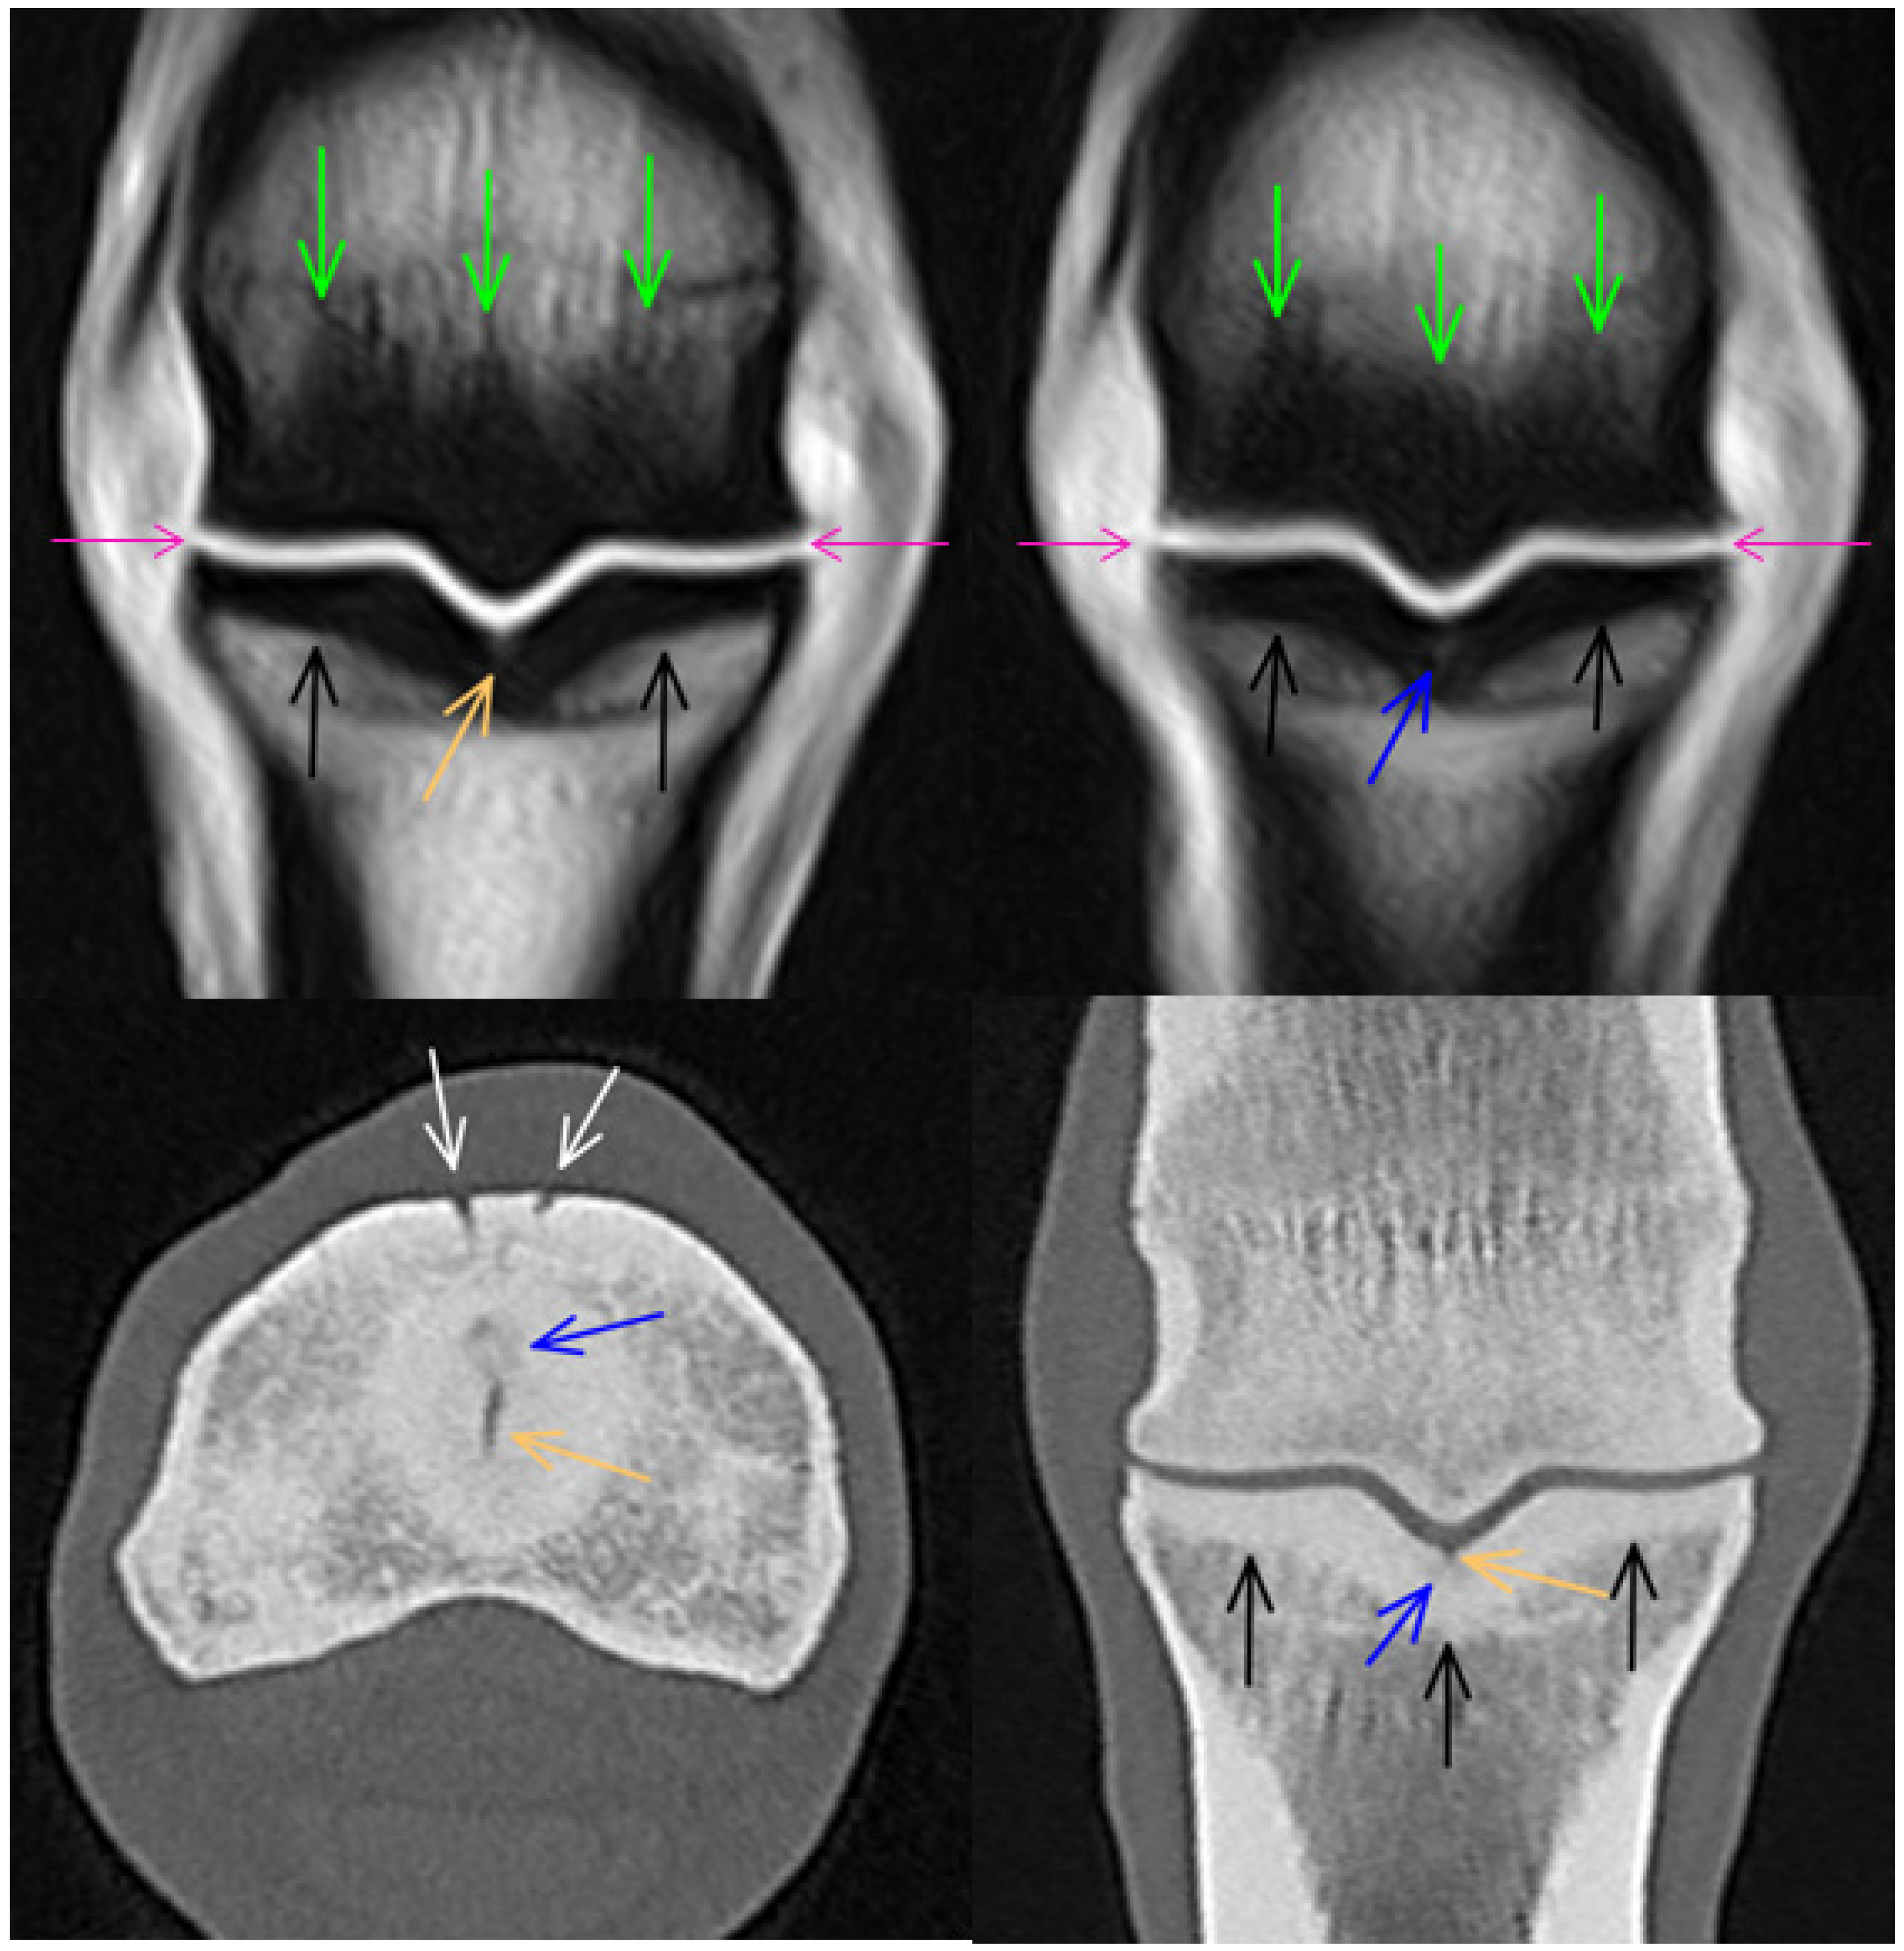

3.1. Third Metacarpal Bone

3.2. Proximal Phalanx